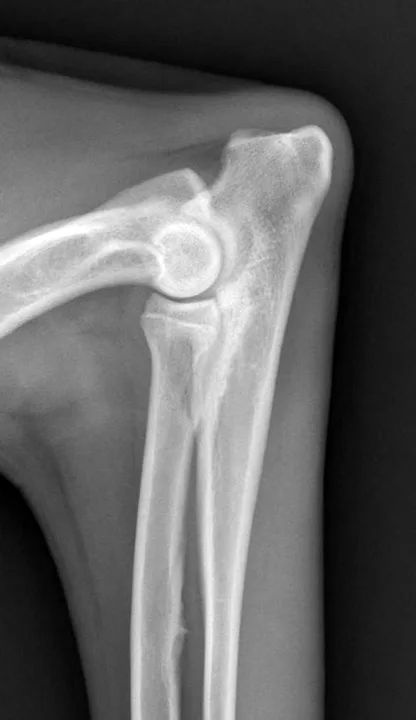

Following examination, Maggie was sedated with dexmedetomidine (3 μg/kg IM) and butorphanol (0.1 mg/kg IM), and orthogonal radiographs of both elbows were obtained. The left elbow appeared radiographically normal on the lateral view, whereas the right elbow had mild subtrochlear sclerosis subjacent to the trochlear notch and apparent loss of detail of the coronoid process (Figure 1). No abnormalities were detected on the craniocaudal view (Figure 2).

Figure 1

Lateral radiograph of the right elbow. Subtrochlear sclerosis and an ill-defined margin or loss of detail of the medial coronoid process can be observed.